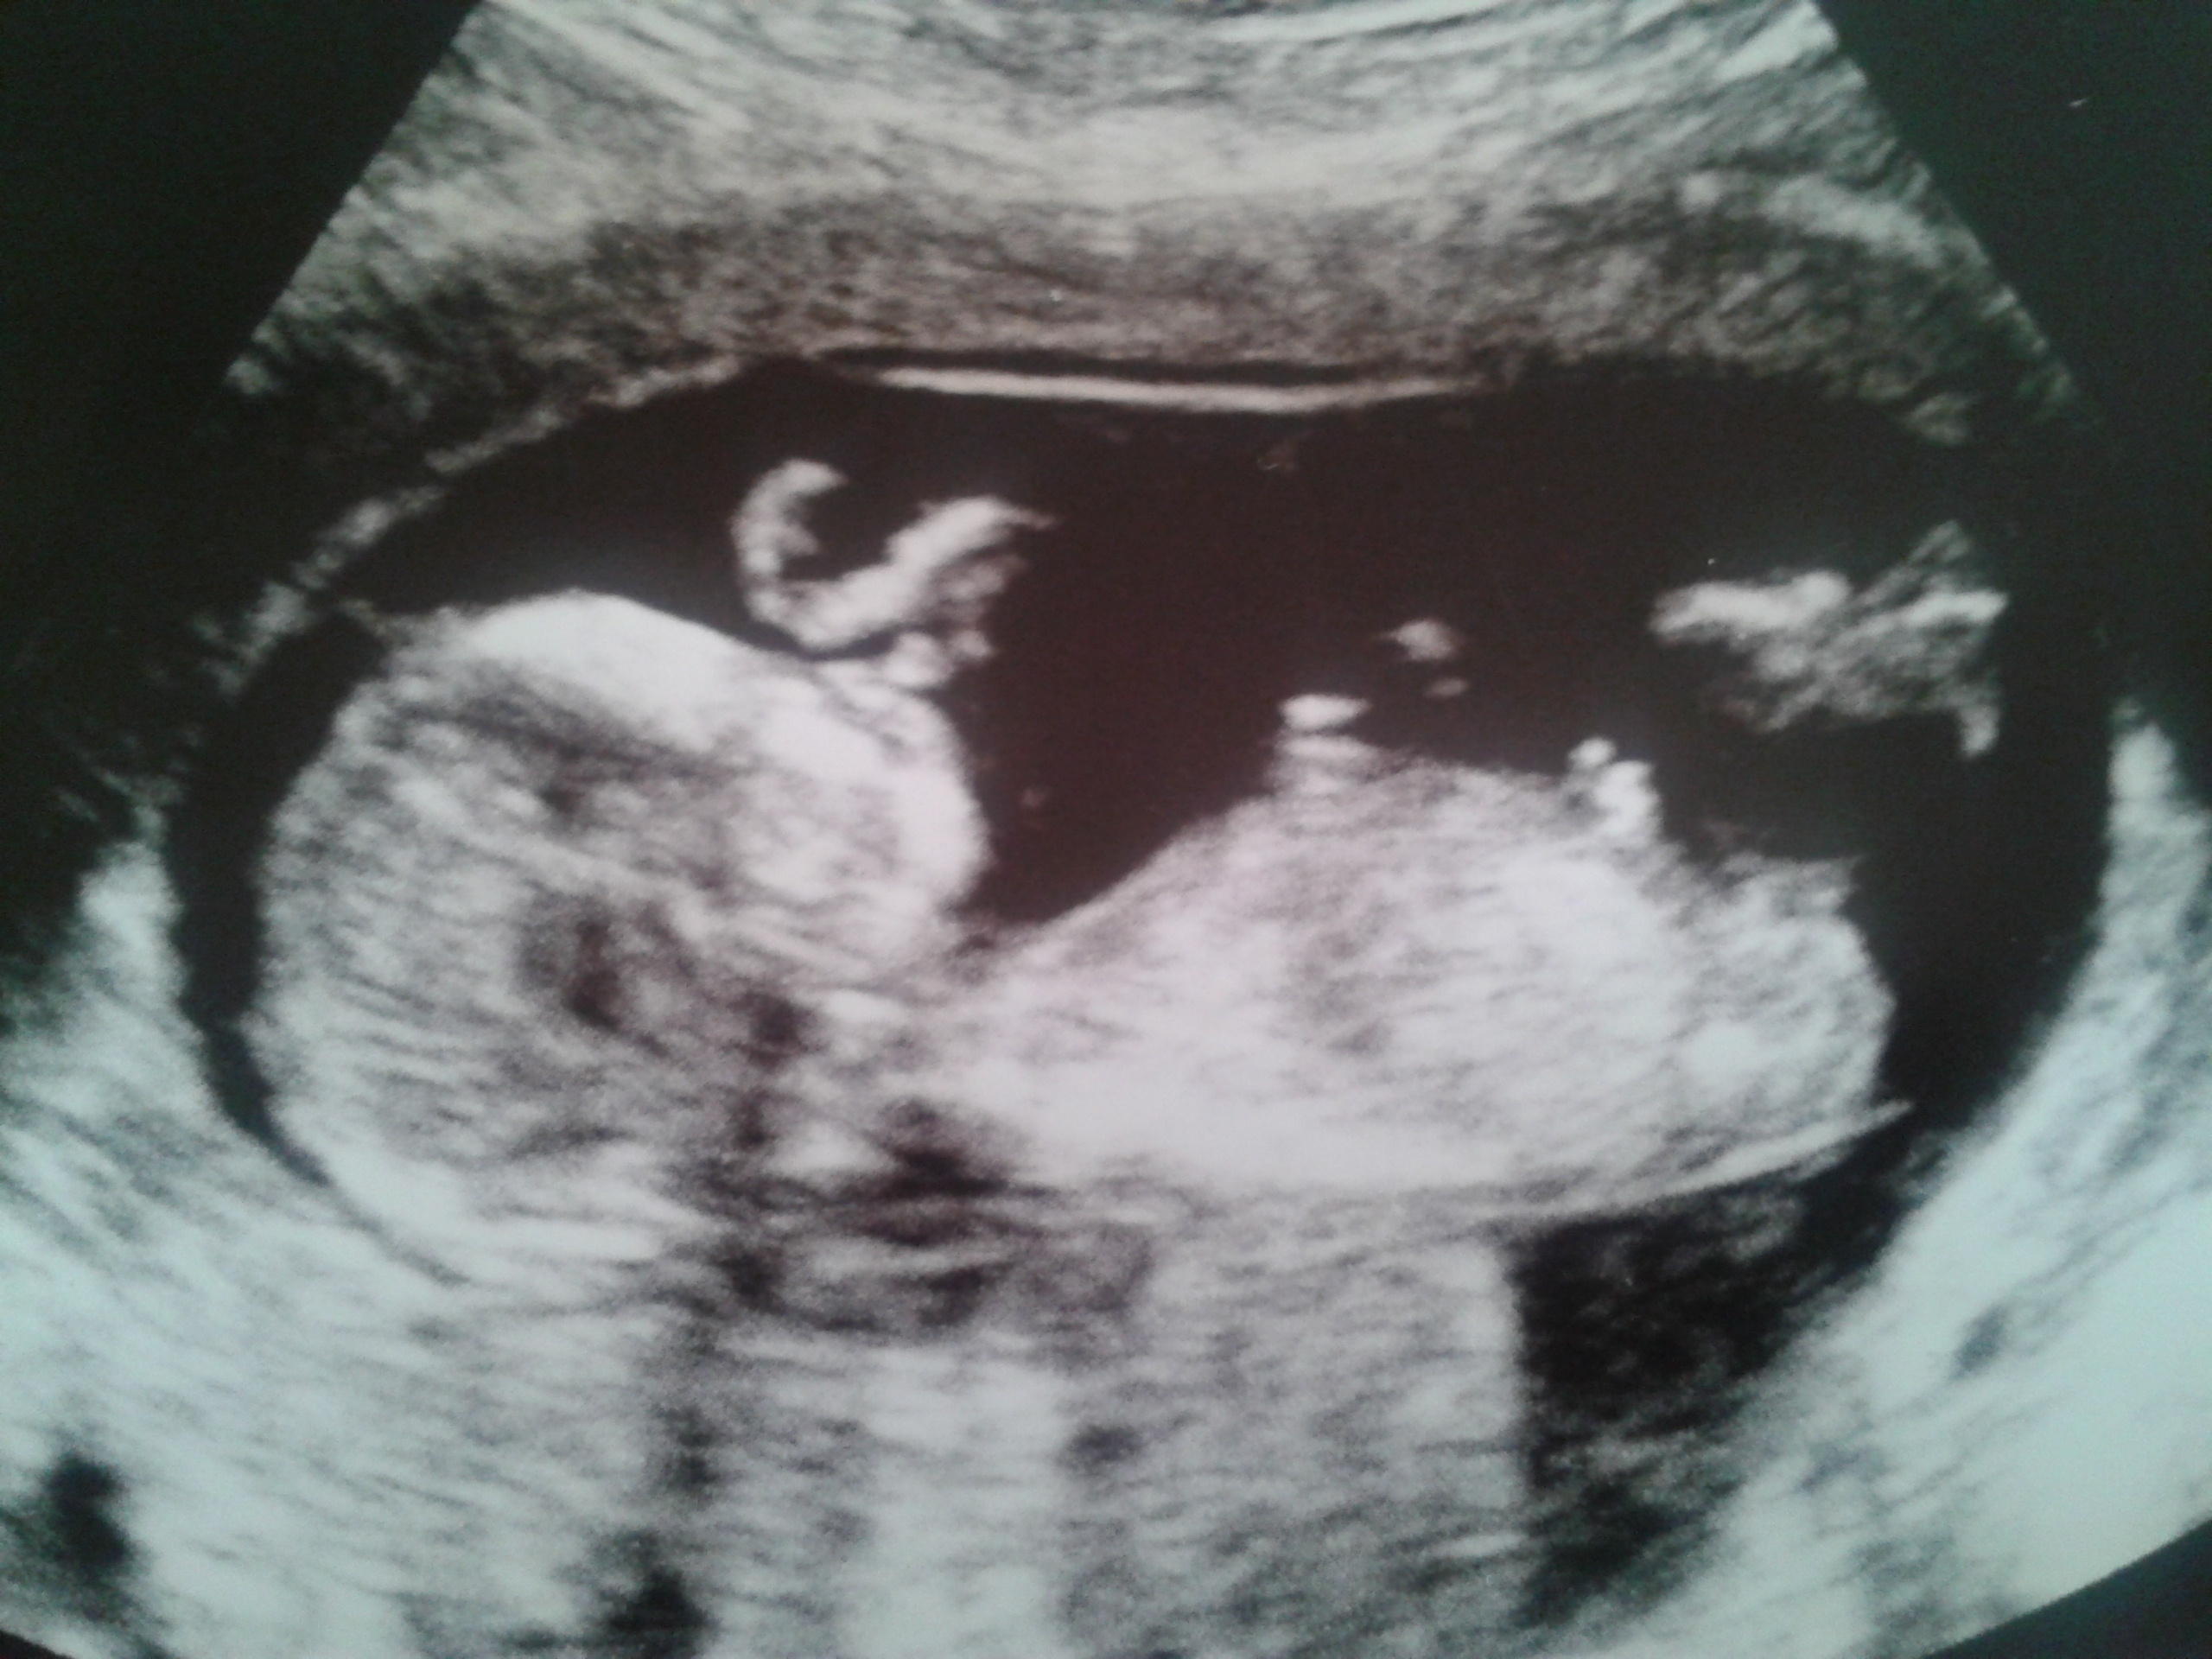

Hi ladies, have a feeling this may be my third baby boy, can anybody see a nub or any other gender clues? Opinions greatly appreciated, I cannot wait to find out! Attachment 15058

I think I can see a nub, not very clear though, but Im going to say Boy!

Weak girl guess x

50/50